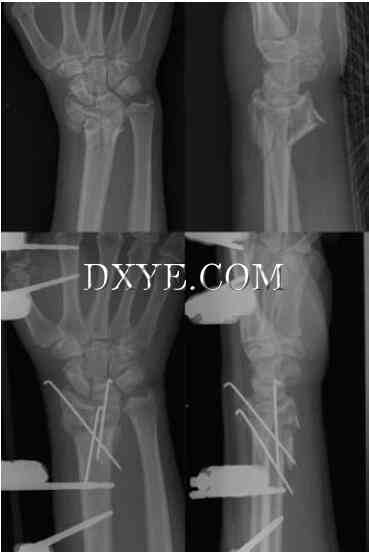

经皮穿针。这种技术适用于可以减少的不稳定骨折,但使用石膏不能保持减少。对于具有显著的干骺端粉碎和/或关节不稳定性的骨折,钉自身是不足的。手术中透视的使用大大提高了针置入的准确性,并可以确定骨折的减少。通常使用1.6毫米(0.062英寸)的克氏针(K-wire)。复位后,克氏针从远端向近端方向进入桡骨茎突末端,穿过骨折到达骨干近端尺侧皮质。一根或两根克氏针可以交叉放置。 Kapandji推广的另一种技术是“口内穿针”。这里克氏针用于减少和维持减少(图76.13)。最初的导线通过骨折部位从桡骨到尺骨的方向引入。一旦导丝到达尺侧皮质,它将作为一个杠杆来提升桡骨碎片以恢复径向高度和倾斜度。然后通过尺骨皮层驱动导线以保持缩小。另一根导线通过骨折部位以90°方向引入到背部至手掌的第一个方向,并以类似的方式用于恢复手掌的倾斜。第三根线可穿过骨折部位穿过桡骨茎突以获得额外的稳定性。

13.jpg

图 76.13.  老年患者关节外桡骨远端骨折内固定术(AO A2型)的Kapandji技术的结果。